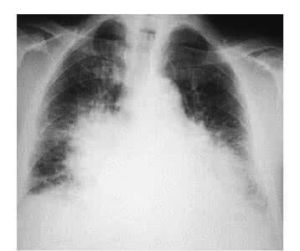

進行心電圖,X線檢查,超聲心動圖,放射性核素與磁共振成像(MRI),運動耐量和運動峰耗氧量測定等檢查。